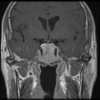

Rad Features of Optic Nerve Meningioma